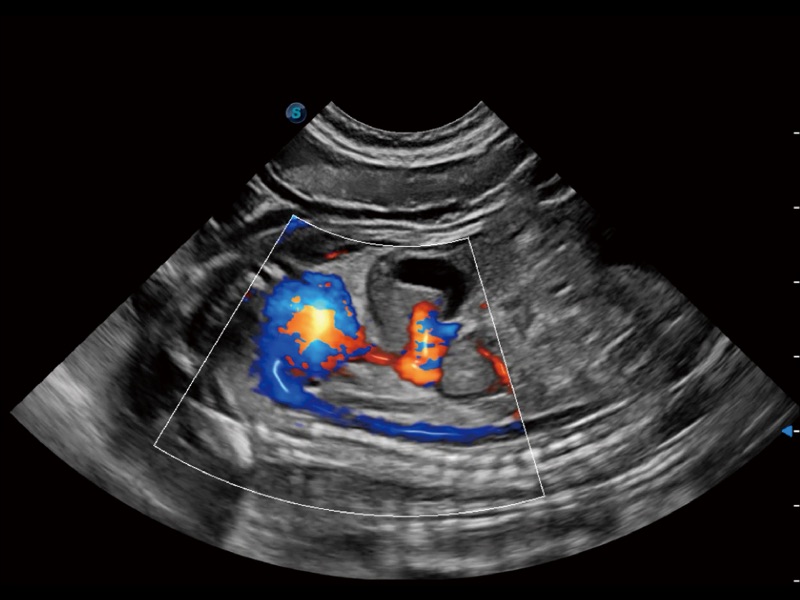

(犬)左室长轴血流

(犬)髂动脉血流

(犬)胎儿主动脉弓立体血流

优异的基础图像

ProPet 70 全新的动物超声智能软件和丰富的探头群,为动物医生提供了高清晰度和精细分辨率的图像,无论在宠物、马科、畜牧还是实验室动物等应用中都可以轻松应对,为您的日常工作带来满意的体验。

• Micro F 显微血流成像

通过创新的 Matrix E自适应滤波器和超长时间域算法,极大提升超低速微细血流的检出能力,同时更精准地滤除软组织和噪声信号,为兽用医生提供以往无法通过常规血流获得的疾病诊断信息。